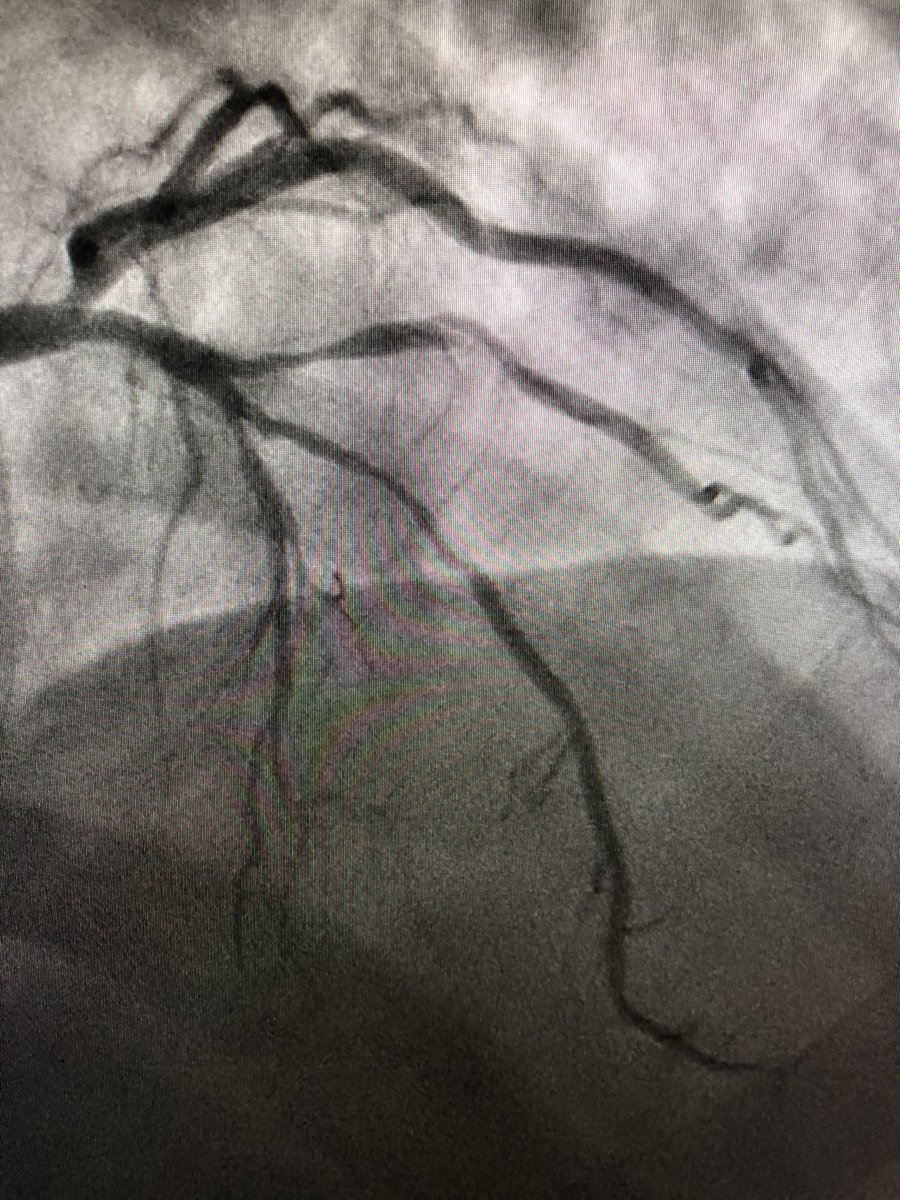

Richard Sohn MD@RSohnMD·

1/ WHY “very late” stent thrombosis? ➡️ #OCT can show you! 👀 CASE: 63M w/ old RCA stent, now w/ sudden severe CP EKG & initial angiography 👇🏼👇🏼